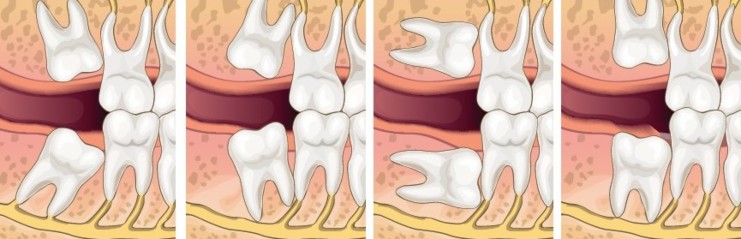

A wisdom tooth may get stuck or develop at an angle if there is not enough space to come through usually, we call this an impacted wisdom tooth.

If a wisdom tooth doesn’t come in properly or there isn’t enough room in your mouth, it can cause complications.

Impacted wisdom teeth can cause infection, pain, inflammation and other issues.